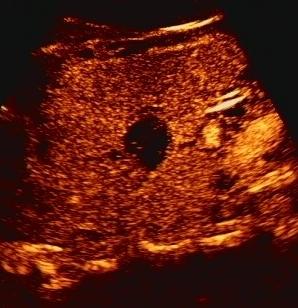

除了CT、核磁增强外,还有超声造影,超声造影也可在动态观察占位的血供情况,从而进一步诊断。